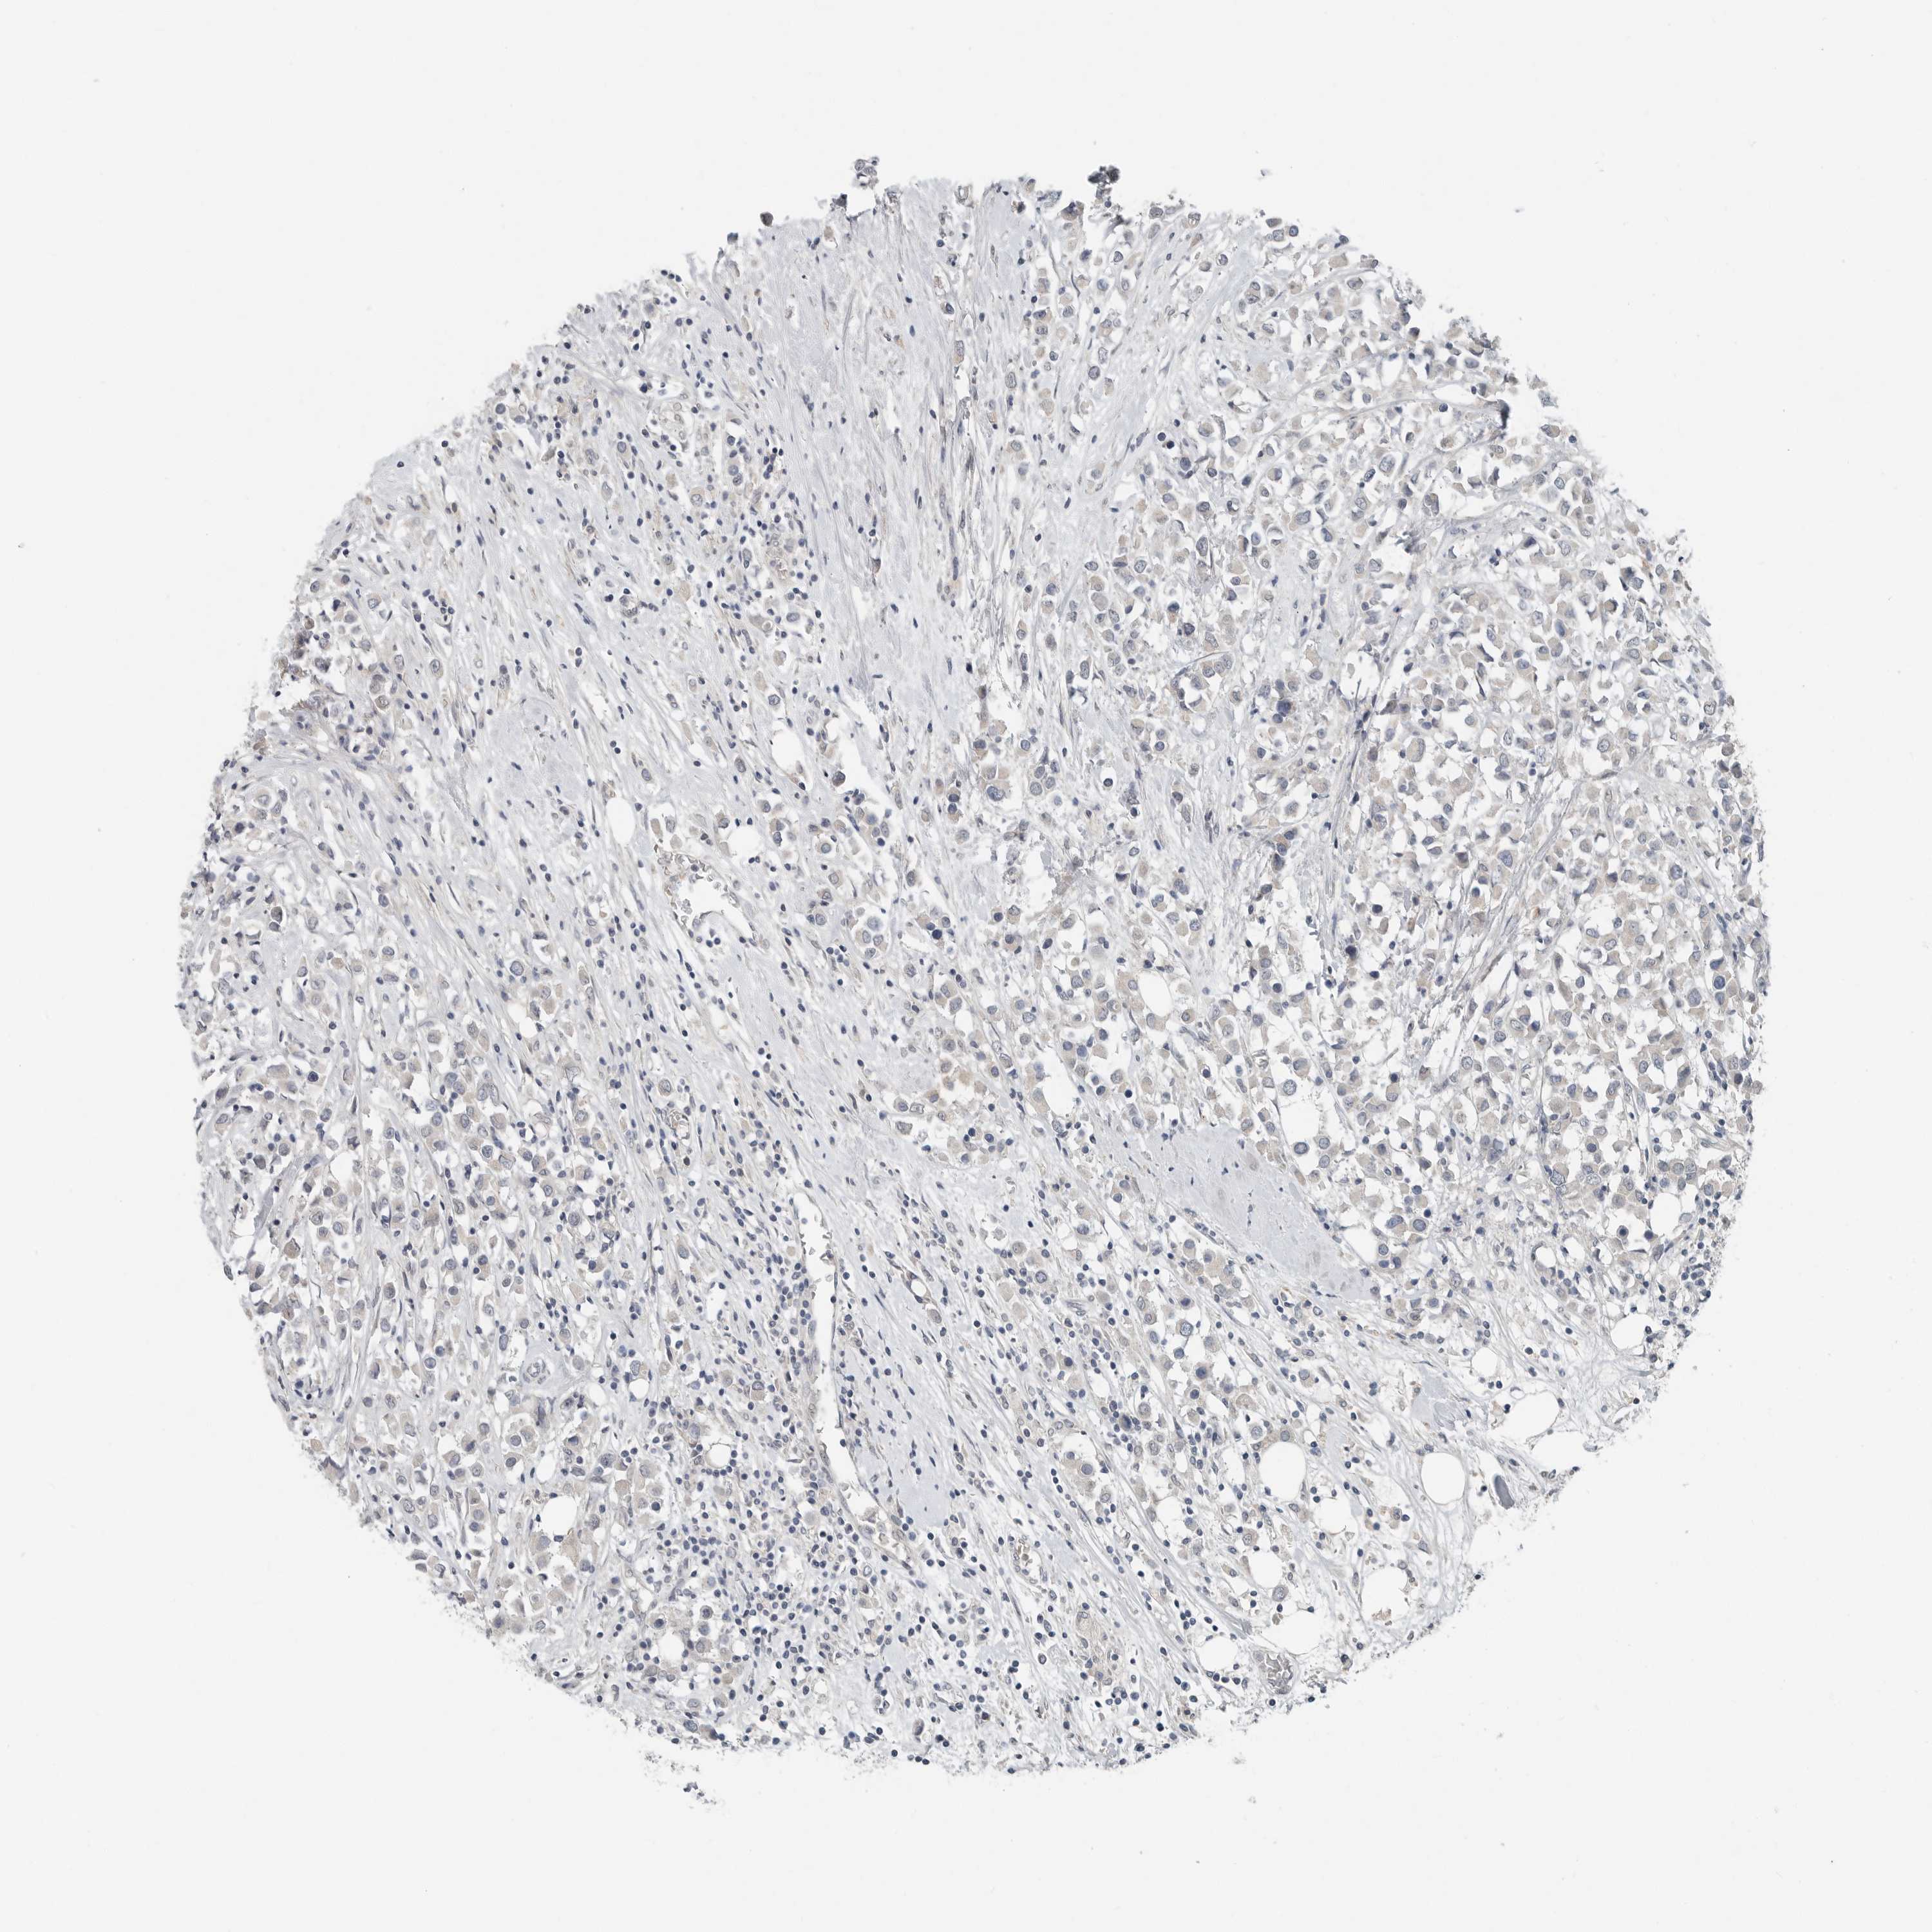

CANCER BREAST CANCER Show tissue menu

BRCA TCGA BRCA VALIDATION PROTEIN EXPRESSION

Breast cancer

Human cancer

Breast invasive carcinoma